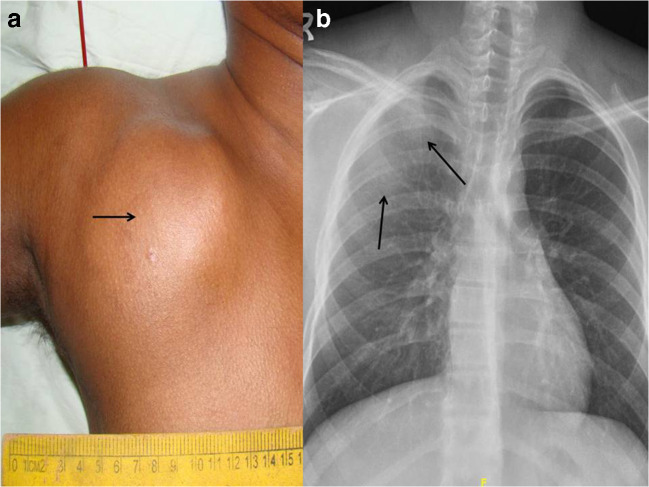

A 16-year-old boy presented with a progressively growing painful swelling over the right anterior chest wall which started immediately after a trauma 10 weeks earlier. On examination, there was a tender and hard 10 cm diameter tumor in the infraclavicular region, restricting shoulder movements (Fig. 1a). Clinically, it was arising from the chest wall, deep to the pectoralis major muscle.

Fig. 1.

(a) Clinical photograph showing the large right pectoral tumor. (b) Chest radiograph showing an ill-defined increased density in the right upper hemithorax (arrows) with no fractures or lytic lesions in adjacent bones

Chest x-ray showed increased density over the right hemithorax with no lytic lesions or fractures in the underlying bones (Fig. 1b). Computerized tomogram (CT) and magnetic resonance imaging were suggestive of a MO, characterized by a well-defined, irregular, heterogeneously enhancing, peripherally calcified mass. It was arising from the chest wall from under the medial third of the clavicle and was growing into the overlying pectoralis major muscle. There were no features of malignancy (Fig. 2a–c). The diagnosis was confirmed by a needle biopsy and the tumor was excised completely. The patient had an uneventful recovery and is doing well 8 months after surgery.